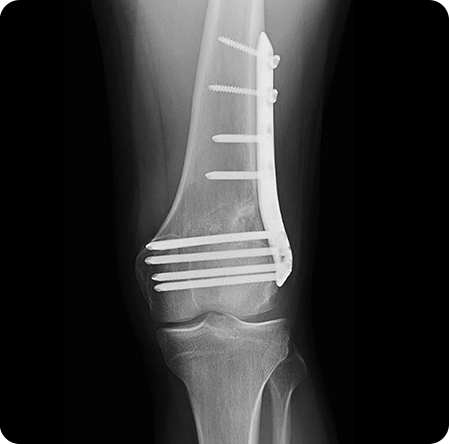

종아리뼈 일부를 절골한 후, 수술 기구를 이용하여 필요한 각도만큼 뼈를 벌려

금속판과 나사를 이용하여 고정합니다.

경골을 절골하여 원하는 각도로 벌려 무게 중심이

바깥쪽으로 옮겨지도록 교정

합니다. 절골한 부위를

금속판과 나사로 고정해 뼈가 안정적으로 붙도록 합니다.